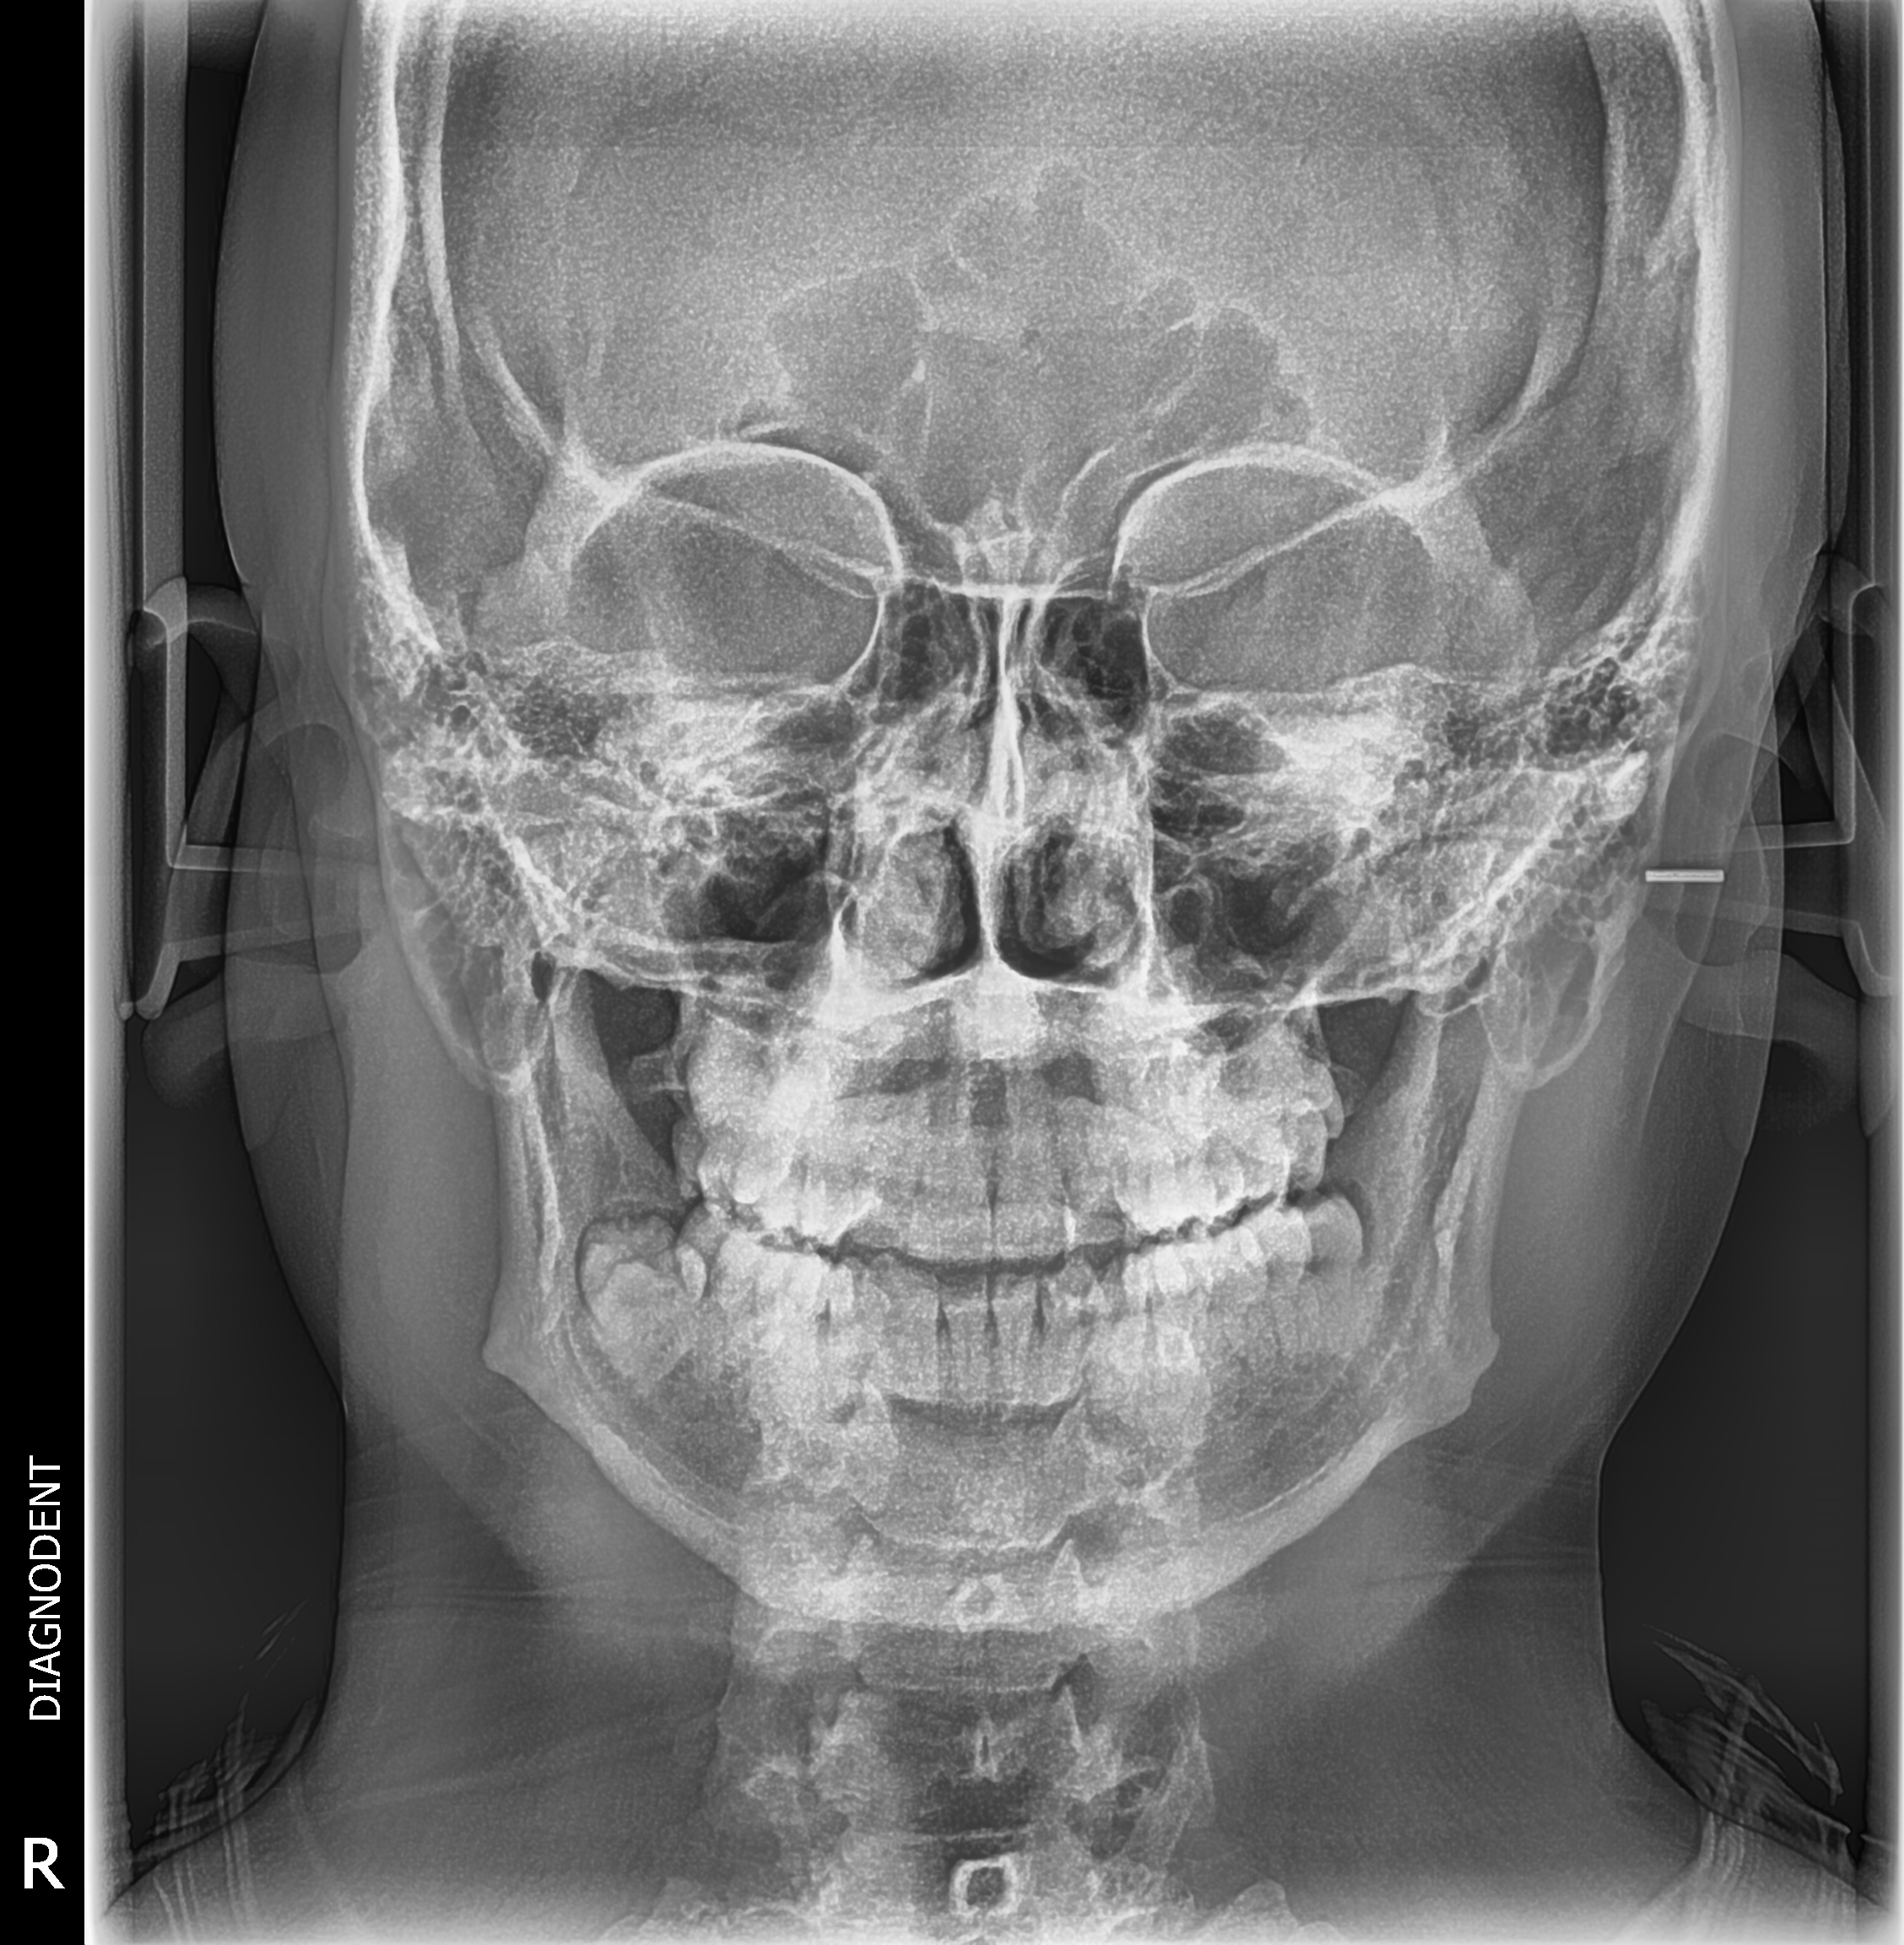

Gracias al Dr. WILMER CERNA, por seguir confiando en nosotros y adquirir su nuevo equipo. Centro ubicado en Carabayllo, instalación de equipo PaX-i SC (Panorámico/Cefalometrico) de la marca VATECH.